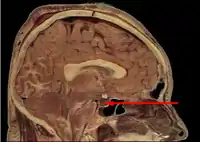

Located at the base of the brain, the pituitary gland is protected by a bony structure called the sella turcica of the sphenoid bone. | |

Structure

In humans, the pituitary gland rests upon the hypophyseal fossa of the sphenoid bone, in the center of the middle cranial fossa. It sits in a protective bony enclosure called the sella turcica, covered by the dural fold diaphragma sellae.[3]

Location of the pituitary gland in the human brain

The arteries of the base of the brain Mesal aspect of a brain sectioned in the median sagittal plane

Mesal aspect of a brain sectioned in the median sagittal plane Pituitary